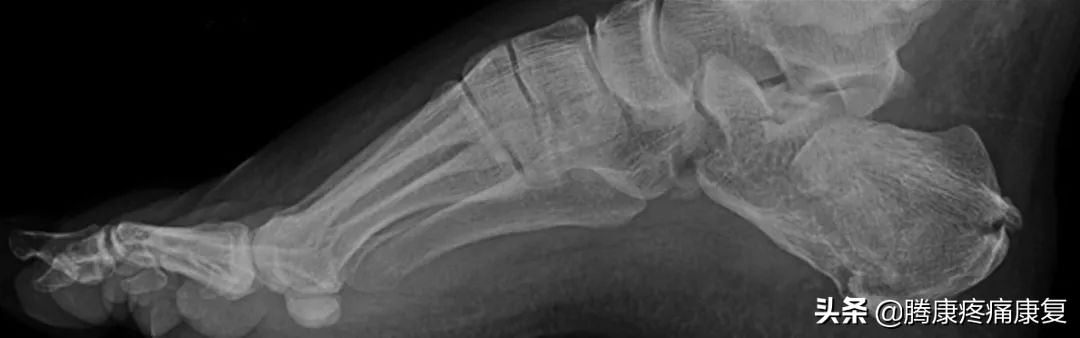

高足弓是什么

高足弓又称为弓形足,这是一种足弓异常升高的形态,当双脚均匀地站立时,由于足弓中部向上抬起,重力全部都集中在脚跟和脚掌上,最终会导致足部疼痛、鸡眼和老茧、足弓僵硬和小腿肌肉紧张。